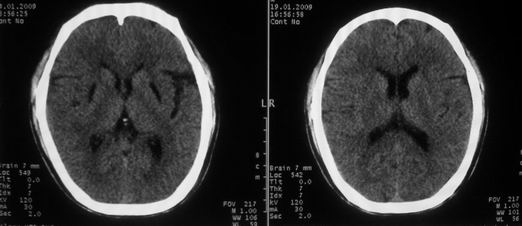

以下是引用随光逐影在2009-1-20 19:38:00的发言:[br]双侧豆状核对称性脑软化灶(中毒性脑病后遗改变?肝豆状核变性?)。

以下是引用jiangjing在2009-1-21 9:38:00的发言:[br]双侧豆状核对称性脑软化灶(中毒性脑病后遗改变?肝豆状核变性?)。